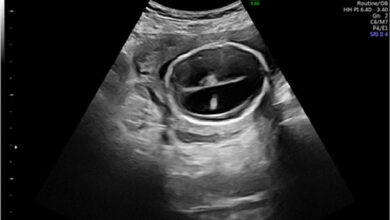

آیا هیدروسفالی در سونوگرافی مشخص میشود ؟

تشخیص هیدروسفالی با سونوگرافی: راهنمای جامع برای والدین و بیماران هیدروسفالی، که در زبان عامیانه به آن “آب آوردن مغز”…

هیدروسفالی جنین چیست و در چند هفتگی مشخص میشود ؟

شنیدن یک تشخیص پزشکی غیرمنتظره در دوران بارداری میتواند برای هر پدر و مادری نگرانکننده و همراه با عدم قطعیت…